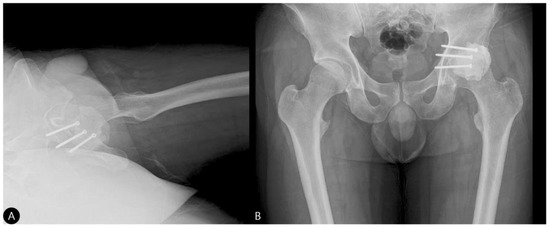

- Reduction and Final Assessment: The hip was reduced under direct vision. Intraoperative fluoroscopy confirmed a concentric reduction, correct implant placement, and the absence of cement fragments in the joint. The stability of the construct was tested through a range of motion. Postoperative imaging confirmed the anatomical reduction and the accurate contouring of the cement construct (Figure 4 and Figure 5).

- Concomitant Injury Management:The tibial shaft fracture was subsequently stabilized with an antegrade intramedullary nail (Figure 6).